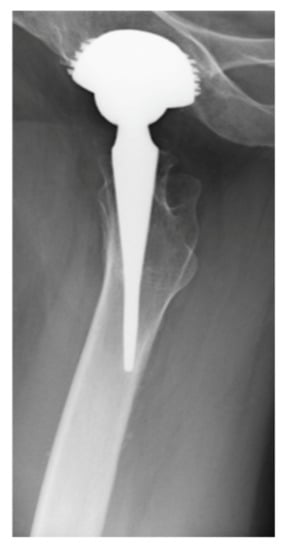

The Rate of Correctly Planned Size of Digital Templating in Two Planes—A Comparative Study of a Short-Stem Total Hip Implant with Primary Metaphyseal Fixation and a Conventional Stem

2. Materials and Methods